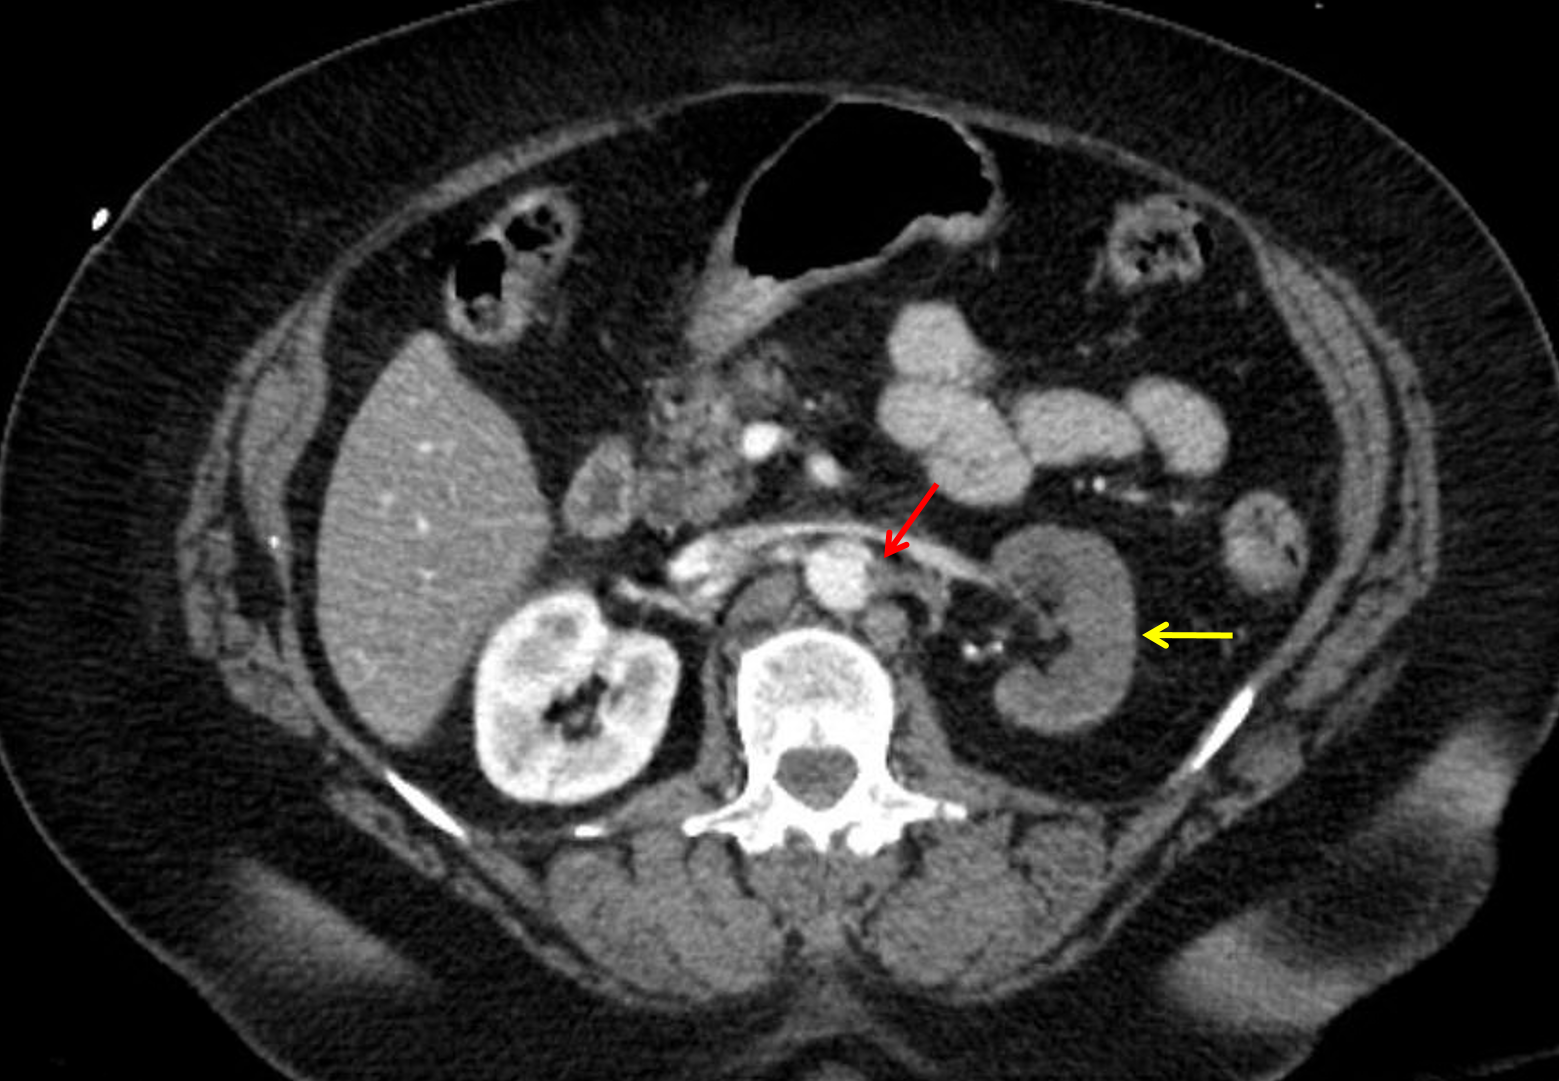

Age: 66

Sex: Female

Indication: Trauma

Additional site of aortic injury just below the diaphragmatic hiatus with extension into and occlusion versus near occlusion of the left renal artery. No large surrounding hematoma. Resultant ischemia of the majority of the left kidney.

Heterogeneous enhancement of the right kidney is likely the result of platelet aggregation in the setting of traumatic aortic injury.

Probable injury of the left common iliac vein.

Flattening of the IVC concerning for hypovolemia.